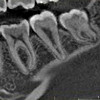

КТ челюсти

Процедура применяется в травматологии, ортодонтии и челюстно-лицевой хирургии для диагностики поражений челюсти и проблем с зубами. Может проводиться повторно в процессе контроля эффективности консервативного лечения до и после операции. Каждая челюсть сканируется отдельно. КТ нижней челюсти позволяет определить ее размеры, расположение нижнечелюстного канала, визуализировать воспалительные и дегенеративные изменения, опухолевые процессы, свищи, абдоминальные образования, сложные переломы, травматические зубы, Черепно-лицевые аномалии развития, включая зубы. КТ нижней челюсти помогает контролировать имплантацию, моделировать челюсть и зубы пациента для изготовления корсетов.

В области верхней челюсти сканирование позволяет определить ширину и высоту костей, оценить внутреннюю поверхность верхнечелюстных пазух и выявить наличие инородных тел и патологических процессов. С помощью компьютерной диагностики, имплантации имплантатов, динамики заболевания, выздоровления в послеоперационном периоде, качество корневых каналов контролируется после установки пломбы. КТ верхней челюсти показана при травмах, нарушениях развития, визуализации положения зубов, которые не могут проникнуть в одиночку, поскольку они находятся под костью или тканью десен, расщелине неба и патологии слюнных желез.

Обе челюсти оцифровывают, чтобы дифференцировать осложнения кариеса, недавние переломы, врожденные и посттравматические деформации, опухоли и абсцесс. Перед пластической операцией, помимо компьютерной томографии нижней челюсти, проводится томографическое исследование частей скелета, которое послужит рабочим материалом для замены отломков, удаленных с лицевого черепа. В результате получаются трехмерные модели, на основе которых они выполняют виртуальную операцию, что значительно облегчает реализацию реального вмешательства.

Расшифруйте результаты, полученные врачом. Через час после манипуляции пациенту дают изображения и заключение, в котором подробно описывается ход сканирования. При расшифровке компьютерной томографии челюсти, диагностика привлекает внимание к интенсивности потемнения, описывает наличие органических изменений и структуру внутриротовых тканей. Отсутствие патологических нарушений в КТ челюсти считается нормой. В случае выявления какой-либо патологии назначается консультация специализированных специалистов, госпитализация или запрограммированная терапия. КТ челюсти имеет неоспоримые преимущества перед другими методами облучения. Он более точный и информативный, он предусматривает прием нескольких сканов, на основе которых создается трехмерное изображение. Доза рентгеновских лучей при компьютерной томографии челюсти ниже, чем при обычной рентгенографии.